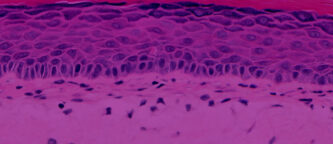

EpiDermFT tissues (Figure 1) are equilibrated overnight under standard culture conditions (37°C, 5% CO2) with EpiDermFT Assay Media (EFT-400-ASY). 18-24 hours later tissue culture media is aspirated and replaced with fresh, pre-warmed media. Under sterile conditions in a laminar flow cell culture hood tissues are equilibrated, with the lid open, for 90 minutes at ambient temperature and relative humidity. Tissues are exposed to topically to 10µl of each test formulation for 60 minutes. Following exposure, residual test formulation is removed from the skin surface using a sterile cotton swab and skin hydration is evaluated by measuring the electrical impedance of the tissue surface (DPM 9003 Nova Meter, Nova Technologies) at time 0 minutes, 15 minutes and 30 minutes post-exposure.